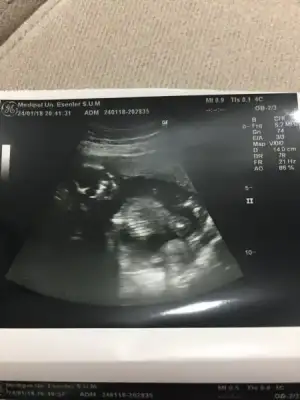

20. hafta net olarak söliyim dedi. başka hiç fikir beyan etmedi dr um :)Özele yazmadıysan gözden kaçmıştır özele yazdıysan da kesin dememişindir yoksa atlamam